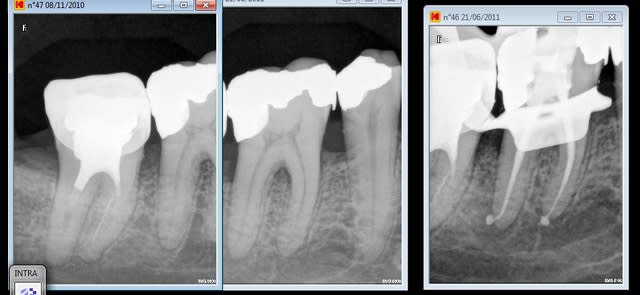

ceci étant le mtwo marche vraiment bien sauf pour les reprises

allez une dernière sympa et pi après j'arrête mais la technique est reproductible .

ah aufait ceramik chez nous ça c'est 81Euros 94 sans la radio tu vois on aime .